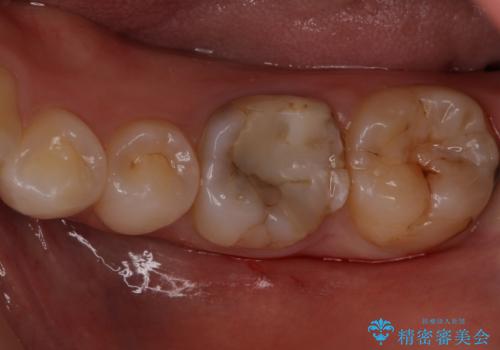

同じような樹脂の詰め物での治療ではまた虫歯ができることが予想されるため、今回はセラミックインレーで修復することとなりました。

以前樹脂を詰めた結果再び虫歯ができてしまっていることから、同じ治療は同じ結果になる可能性があるため今回はアプローチを変えてセラミックインレーで修復処置をしていくこととなりました。

適合の良い修復物を入れることは今後の虫歯リスクを抑えることに繋がります。